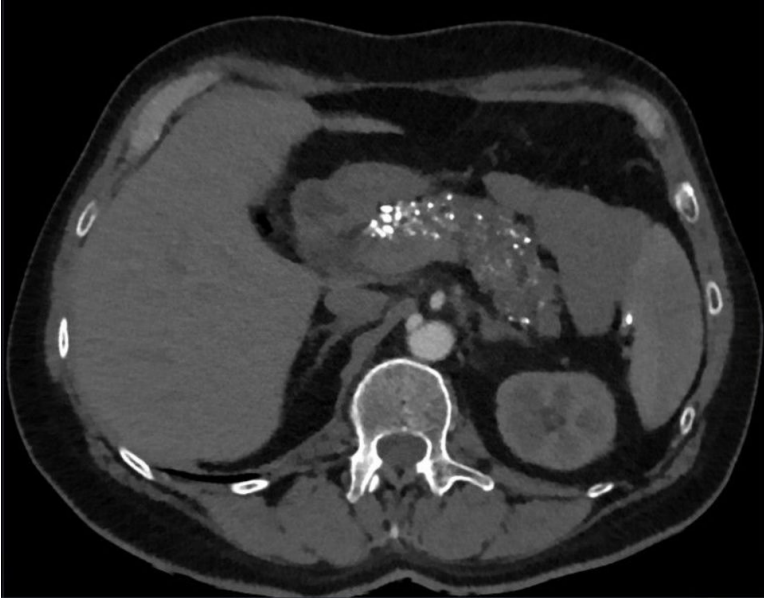

What do you expect to see on imaging for chronic pancreatitis?

A

• Calcification of pancreas

• Change in size (atrophy or enlargement)

• Fibrosis (hyperechoic)

• Pseudoaneurysms, pseudocyts

• Dilation of pancreatic duct

Diagnosis of acute pancreatitis requires 2/3 features: 1. Acute onset severe epigastric pain 2. Elevated amylase/lipase 3. CT imaging (or MRI)

Diagnosis of acute pancreatitis requires 2/3 features: 1. **Acute onset severe epigastric pain** 2. **Elevated amylase/lipase** 3. **CT imaging (or MRI)**